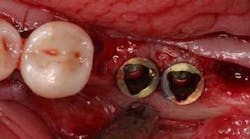

An unfortunate occurrence in dental implant prosthetics is malpositioned implant placement. In fact, a large percentage of my dental laboratory business has been restoring “rescue cases,” which are usually either new cases or remakes of seemingly unrestorable implants

There are various methods for restoring these prosthetic problems, one of which is the cementable option. The custom abutment dates back to the 1980s. This was directly related to poorly placed implants for which doctors had no possible means of restoring, due to a lack of angle-correcting abutments from manufacturers. We lab technicians had to find ways to make these cases work, such as making a custom abutment out of the titanium alloy impression coping for the Core-vent implant or using the UCLA abutment from Implant Innovations. The cementable option became the only one for many dentists due to their familiarity with standard crown and bridge and the lower cost. However, cementable restoration has come under fire in the last few years due to cement-induced peri-implantitis and other controversial claims. So in the case of a screw-retained prosthesis where the implants are malpositioned, we have quite a few options.

2. A custom abutment with a milled lingual screw hole is an option when the manufacturer does not make an abutment or the position is too buccal or too deep. In this situation, the custom abutment can be made in the traditional way as any cementable prosthesis with a labial chamfer or butt. After finishing the abutment, a lingual screw hole is tapped with a specific-sized tap that corresponds to a screw. A plastic waxing sleeve and screw is attached to the abutment, and an over-coping is waxed. When completed, the coping is now screw retained. The drawbacks to this system are: